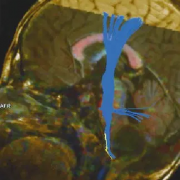

脑干肿瘤在成年患者中并不常见。出现的平均年龄是生命的四个十年,总生存期约为54-64个月。它们在流行病学数据中占全部脑肿瘤的小于2%。那些仅位于延...

延髓胶质瘤属于脑干胶质瘤的异质组。这些肿瘤起源于髓质,并可延伸至邻近结构,如脑桥、小脑下梗、小脑和脊髓上部。脑胶质瘤发生在儿童和成人患者...